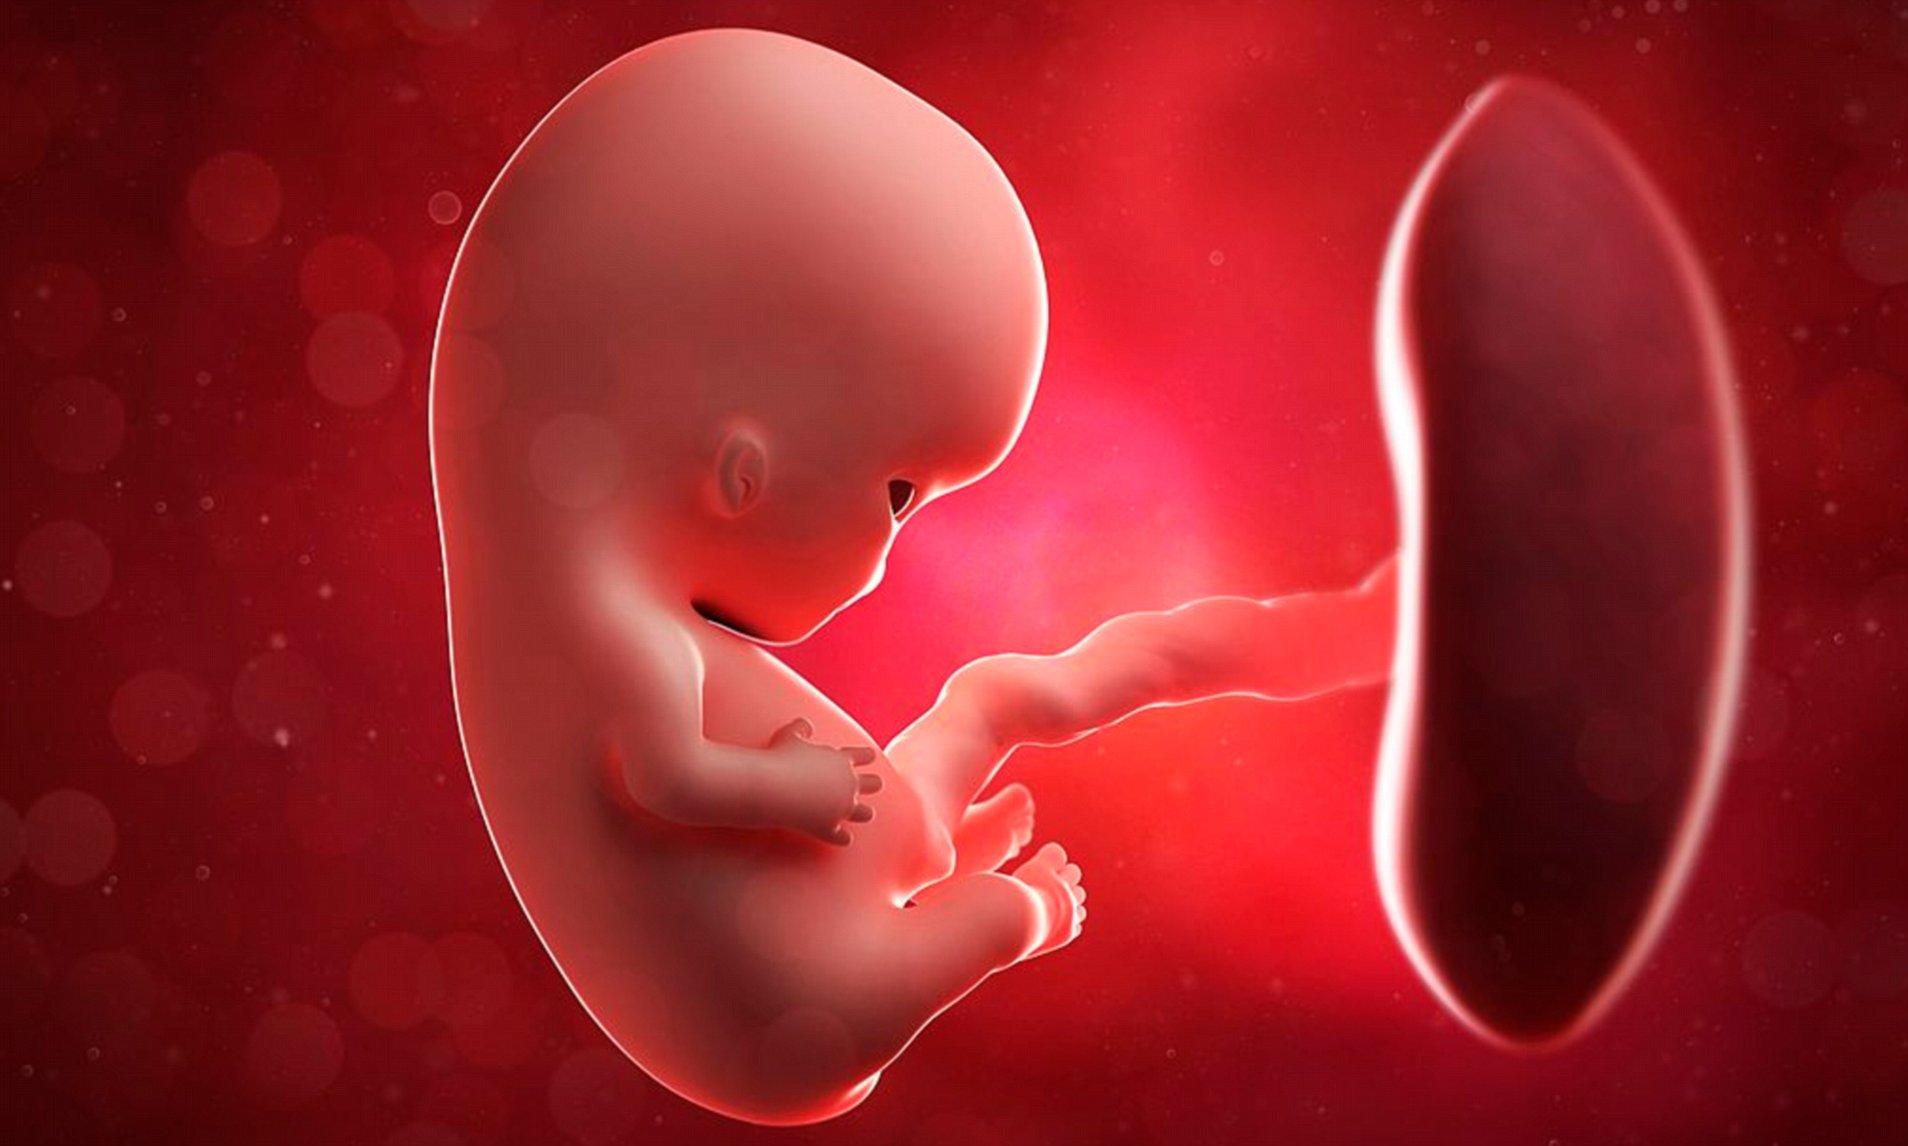

新生命是父與母的結合,基因的組成亦源於雙親。英國劍橋大學最新發現,在母體內的胎兒會透過一個來自父親的基因,指揮胎盤釋放荷爾蒙訊號,從而改變母體的代謝機制,達到「遙控」母體的營養分配、確保自身正常發育的目的。

一直以來,大家普遍認為母體會自動調整體養分配支持胎兒發展,但劍橋大學的研究則揭示,仍在成長的胎兒不是被動的接受者,而是會經由遺傳自父親的基因,主動向母體尋求更多養分,形成一場微妙的營養分配戰。因為胎兒在爭取養分的同時,母體也需要在供養胎兒與自身健康間取得平衡。

胎盤會釋放特定荷爾蒙與母體溝通,從而使母體優先將營養輸送給胎兒。

研究指出,在這場攻防戰中,胎盤扮演關鍵及不可或缺的角色。因為胎盤會釋放特定荷爾蒙與母體溝通,從而使母體優先將營養輸送給胎兒。而以懷孕老鼠進行的實驗亦確認胎盤釋放訊號影響母體代謝的機制。

專家稱,這是首個直接證據表明來父親的基因,會透過胎盤向母親發送訊號,從而改變營養分配,反映來自父系的基因通常會促進胎兒生長,母系基因則傾向限制胎兒成長,避免過度消耗母體資源或因胎兒過大而增加分娩風險。